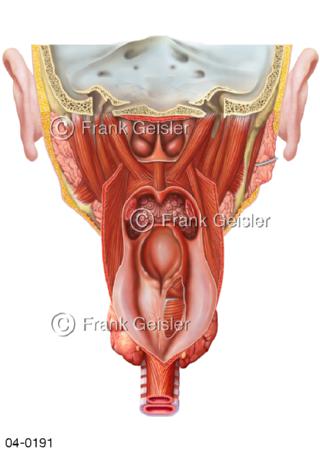

Bildergalerie Topografie Organe

Bilder zur topografischen Anatomie, die Lage der Organe und die Strukturen nach ihren räumlichen Lagebeziehungen zueinander, Übersicht der inneren Organe im Kopf und im Rumpf, Topografie der Organe im Brustraum (Thorax) und im Bauchraum (Abdomen)